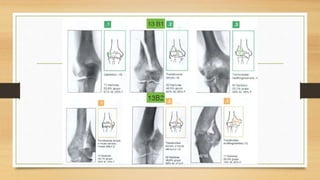

MEHNE Y JUPITER PARA

FRACTURAS ARTICULARES

EN H Y LAMBDA TIENE

MAYOR RIESGO DE NECROSIS

AVASCULAR